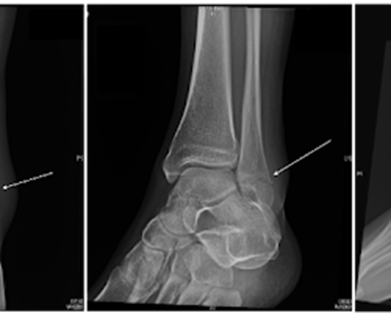

An ankle fracture is a break or crack in one or more of the bones that make up the ankle joint. The ankle joi…